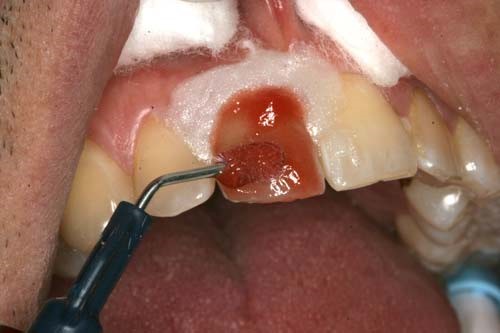

Internal bleaching is a method for brightening a tooth from the back to front. Initial, a root canal is performed to expel any pulp that is infected. At this point, sodium perborate paste is put within the tooth. This material responds with stains and breaks down their particles, causing the teeth to seem whiter. After a root canal, your tooth is fixed to prevent further damage.

WHAT IS THE PROCEDURE OF INTERNAL BLEACHING?

The fading process differs significantly if the tooth is stained in light of an earlier root canal treatment. Also, a patient might be sent home with bleaching trays to additionally improve whitening.